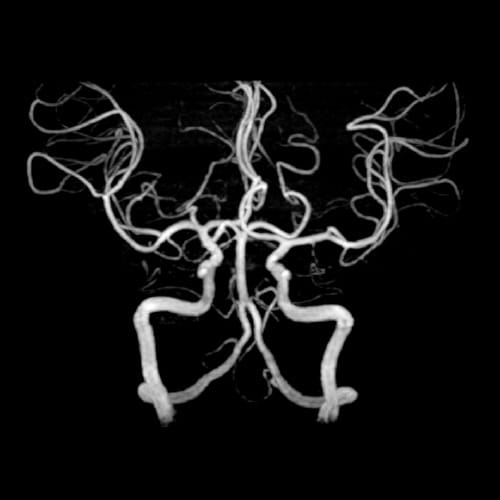

脳MRA(血管撮影)

脳MRI

脳の血管を撮影し3次元的に観察することで、脳動脈瘤や血管の狭窄・閉塞、血管奇形の有無を確認します。

将来的な脳卒中リスクの把握に重要な検査です。